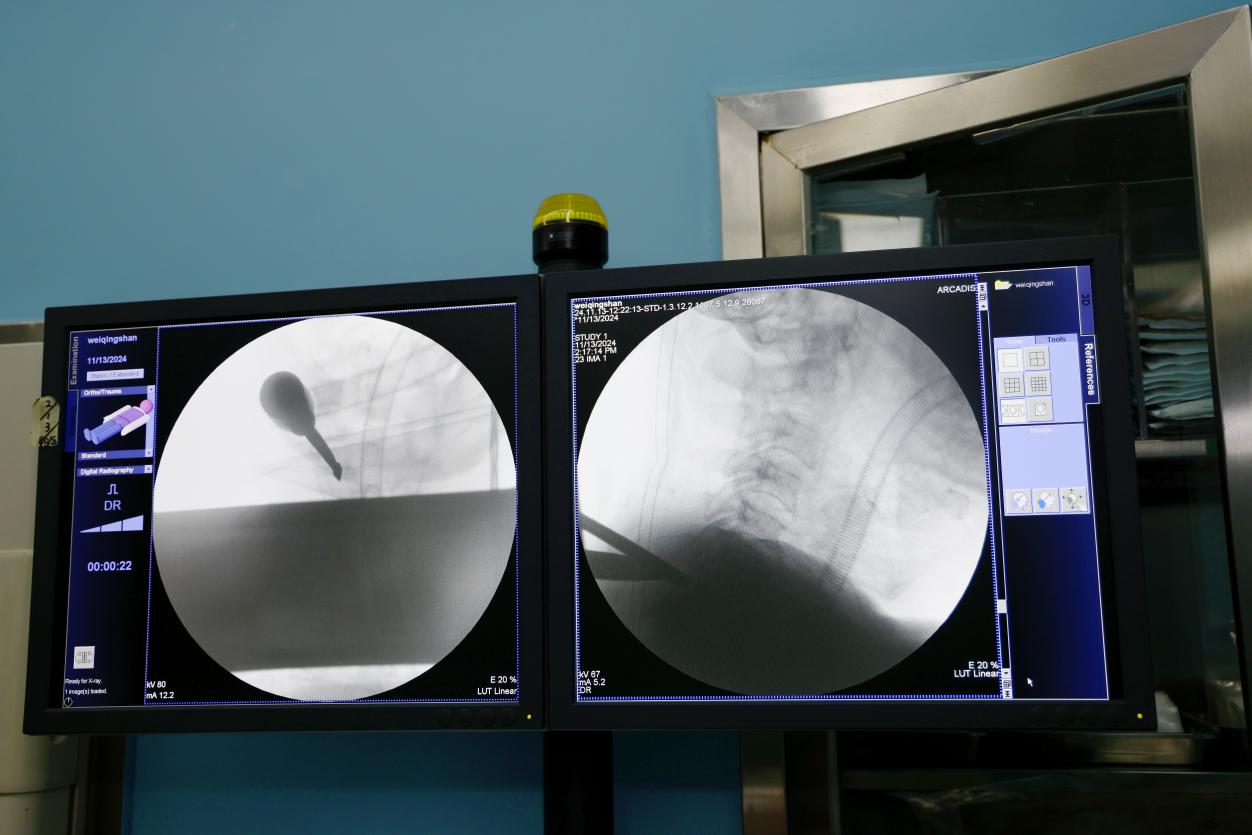

近日,北京中医药大学东方医院骨科顺利开展了东方医院首例单侧双通道脊柱内镜(UBE)颈椎间盘髓核切除手术,标志着医院在脊柱微创治疗领域迈出了重要的一步。

手术的患者是一名65岁的男性,因为颈6-7椎间盘突出,脱出的髓核压迫了相应神经根,引发左肩及左上肢剧烈疼痛和麻木感,活动明显受限,严重影响了生活质量。为尽快缓解患者的疼痛,早日康复恢复正常生活,骨科主任李运海与副主任医师王亚非在对患者进行全面且详细的身体检查和综合评估后,决定采取“单侧双通道脊柱内镜下颈椎间盘髓核切除术”微创手术治疗方案。因为颈椎周边分布有许多重要的血管和神经,手术操作复杂,风险大。然而,经过骨科团队的精心准备和紧张有序的手术操作,患者术后疼痛症状消失,目前已顺利出院。

近年来,北京中医药大学东方医院骨科相继开展了大量“单通道”脊柱内镜手术,“双通道”内镜已经在腰椎椎管狭窄等疾病手术上开展。此次成功开展双通道脊柱内镜下颈椎手术,不仅扩大了脊柱微创的手术领域,也使骨科在微创手术治疗方面又迈上了一个新台阶。未来,科室也将不断探索新技术,不断提高硬实力,为更多患者带来福音。